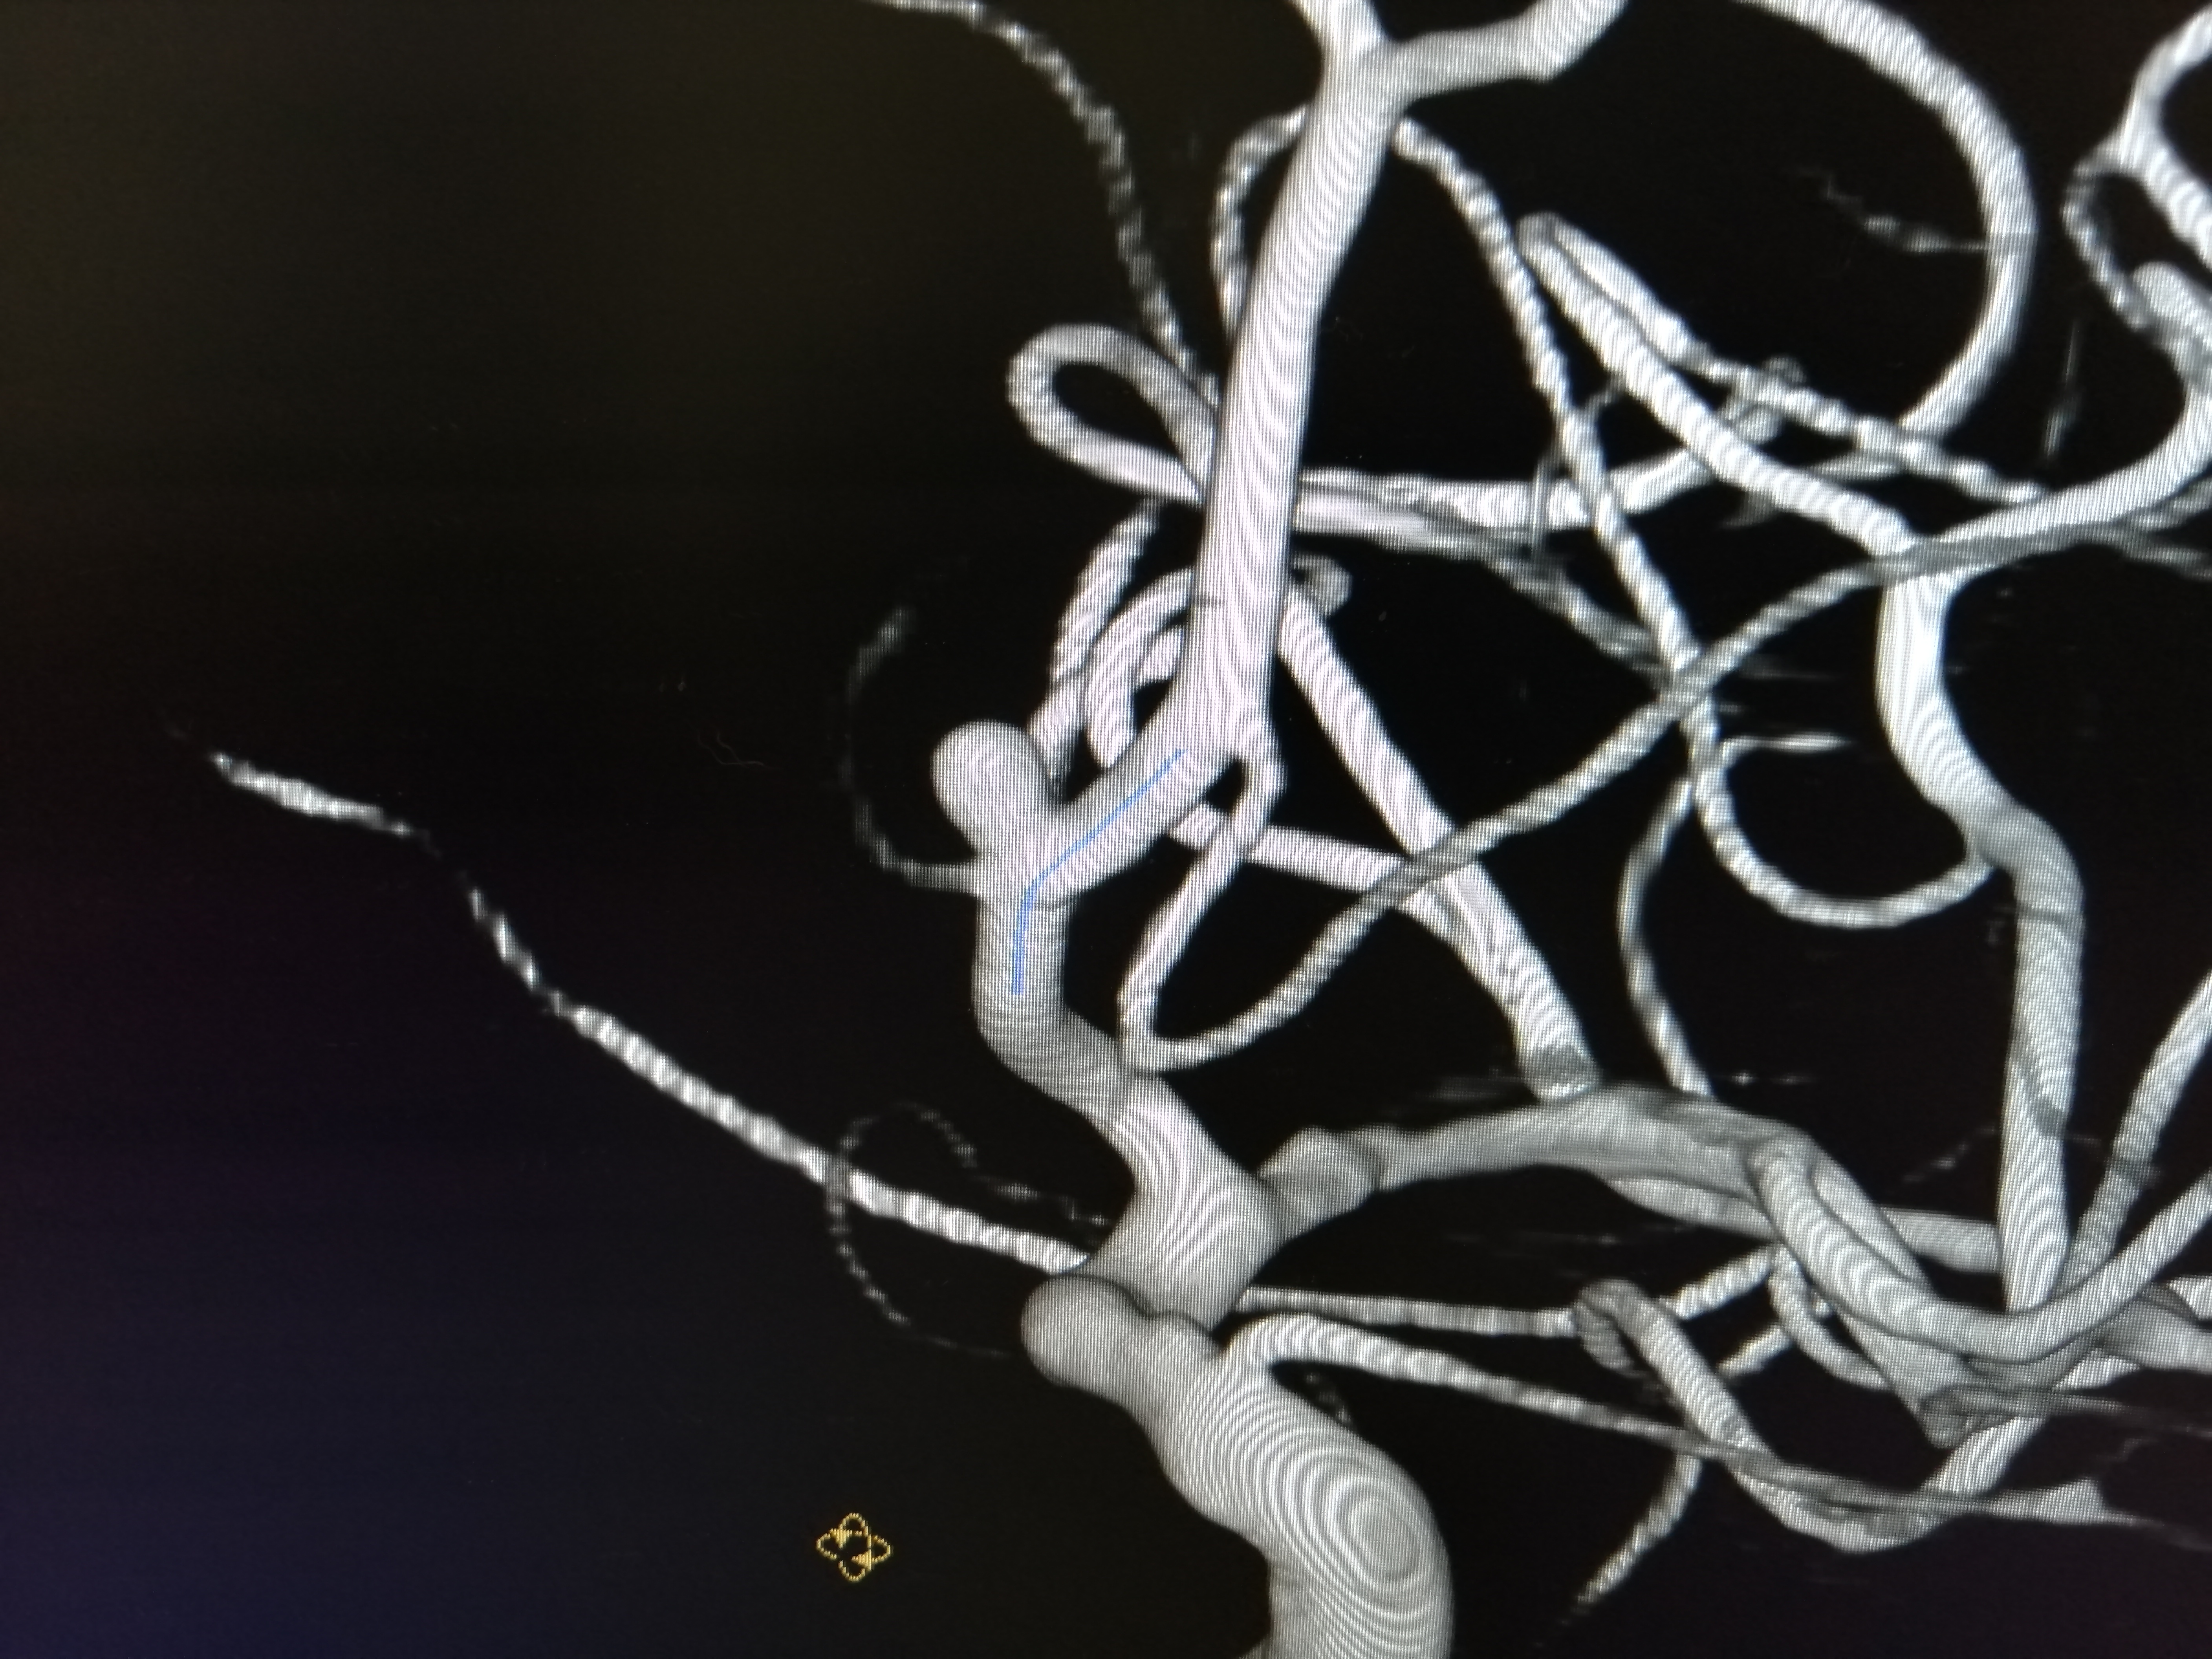

-К шейному и внутричерепному сосудам достаточно было одного доступа – через бедренную артерию. Сначала работали со стенозом - он затруднял доступ к аневризме, расположенной выше по кровотоку. Стентирование сонной артерии само по себе непростое вмешательство с использованием большого набора инструментов. Например, здесь необходимо устанавливать так называемые ловушки для тромбов, чтобы исключить их попадание в кровоток. Сложность в лечении аневризмы была связана как с её размерами – всего 3 миллиметра в диаметре, так и дистальным расположением – дальше «Виллизиева круга». При этом у неё оказалась достаточно широкая шейка, которая не смогла бы удержать микроспираль – специальную мягкую проволоку для заполнения мешка аневризмы и предотвращения дальнейшего поступления туда крови. Пришлось применить особую ассистирующую, то есть вспомогательную методику – с использованием специального микробаллона. В общей сложности операция заняла 2 часа 10 минут, - рассказывает рентгенохирург Екатерина Иванкова.